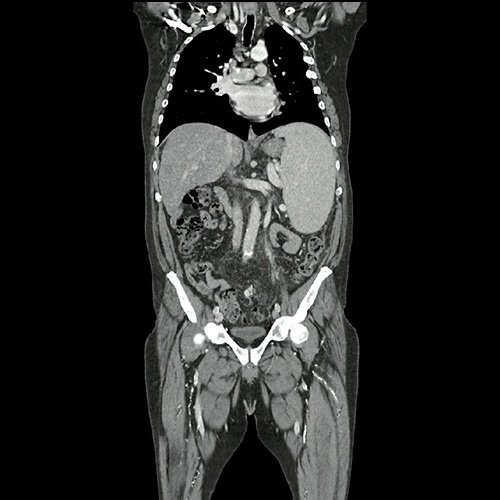

• TAC de abdomen y pelvis con contraste EV (08/25): Se carecen de estudios previos. Se observa hígado de contornos irregulares, con hipertrofia en el lóbulo caudado y el lóbulo hepático izquierdo, con características de hepatopatía crónica, con esteatosis hepática difusa y un patrón de tinción heterogéneo con contraste, no evidenciándose lesiones focales en este examen. Se acompaña este hallazgo de marcada esplenomegalia, homogénea, con un bazo que mide 19 centímetros de diámetro vertical, se observa ingurgitación con prominentes estructuras venosas correspondientes a vena esplénica, circulación colateral venosa periesplénica, y shunts esplenorrenales. La vena porta también se observa aumentada de calibre, con un diámetro de 19 milímetros a nivel del hilio hepático. Vesícula esclero-atrófica con múltiples litiasis que moldean la luz vesical. No se observan lesiones en el páncreas, glándulas suprarrenales y riñones, se observa efecto de masa del bazo sobre el riñón izquierdo. Llama la atención marcada alteración con reticulación de la grasa peritoneal, tanto en el peritoneo anterior como principalmente engrosamiento de las fascias lateroconales y del peritoneo posterior, que se extiende por la grasa mesentérica hacia la pelvis, con ingurgitación de estructuras vasculares venosas pelvianas dependientes de la mesentérica inferior hacia la vena esplénica. No se observa ascitis al momento del examen. El tubo digestivo muestra el estómago colapsado de paredes no evaluables. El colon muestra abundante materia fecal, se observa un área de engrosamiento parietal del colon sigmoides que en primera instancia interpreto como falta de distensión. No se observan adenomegalias, existen ganglios aumentados en número a nivel del mesenterio y del retroperitoneo. No se observan adenomegalias ilíacas o inguinales. Severa ateromatosis de la aorta abdominal y sus ramas. Se observa menor flujo en la vena femoral y vena ilíaca externa izquierda respecto de la contralateral, si bien no es un estudio angiográfico, sugiero cotejar con eco doppler. Vejiga de paredes finas. Las estructuras óseas muestran incipientes espondiloartrosis y cambios degenerativos facetarios.

Tomografía de abdomen y pelvis con contraste. Corte coronal. VER CUAL